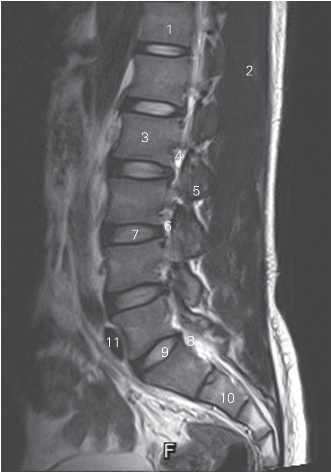

图3-13 经脊柱腰、骶尾段的旁正中矢状断层MR T2加权图像

1 第12胸椎椎体 12th thoracic vertebral body

2 竖脊肌 erector spinae

3 第2腰椎椎体 2nd lumbar vertebral body

4 第2腰神经 2nd lumbar nerve 5 乳突 mastoid process

6 椎间孔 intervertebral foramen

7 第3腰椎间盘 3rd lumbar intervertebral disc

8 第1骶神经 1st sacral nerve

9 第5腰椎间盘 5th lumbar intervertebral disc

10 第2骶椎椎体 2nd sacral vertebral body

11 髂总动脉 common iliac artery